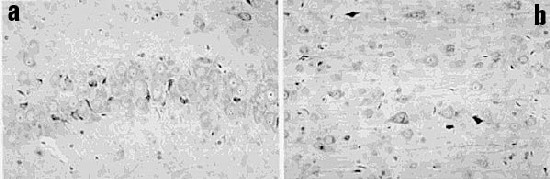

Fig.2 :

a: Rangée de cellules nerveuses dans une coupe de la bande des cellules pyramidales de l'hippocampe dans le cerveau d'un rat exposé aux micro-ondes de téléphonie mobile. Parmi les cellules nerveuses grandes et bleu-pâle, il y a des cellules nerveuses noires et contractées intercalées, appelées "neurones sombres". La photo prise au microscope résulte d'une coloration de la coupe au violet de crésyle et est à fort grossissement.

b: Le cortex d'un cerveau de rat exposé aux micro-ondes d'un téléphone mobile montre les cellules nerveuses normales bleu-pâle, mélangées à des "neurones sombres", anormaux, noirs et contractés, à toutes les profondeurs dans le cortex, mais moins nombreux dans les couches supérieures (en superficie). La photo prise au microscope résulte d'une coloration au violet de crésyle et est à fort grossissement.

Les neurones sombres dispersés et groupés révélés par la coloration du violet de crésyle , qui étaient souvent rétrécis et colorés en foncé, se fondaient dans un aspect homogène avec perte des structures internes des cellules. Quelques uns de ces neurones sombres étaient aussi positifs à l'albumine ou montraient des microvacuoles indiquant un processus pathologique actif. Il n'y avait pas d'hémorragies, ni de réactions gliales, astrocytiques ou microgliales discernables, adjacentes aux neurones modifiés. Des neurones modifiés ont été observés à tous les endroits, mais spécialement dans le cortex, dans l'hippocampe et dans les ganglions basaux. Ils sont mélangés parmi des neurones normaux (fig. 2). Le pourcentage de neurones anormaux a été grossièrement évalué au taux d'environ 2 %, mais il est plus apparent dans quelques zones restreintes de la figure.

Nous présentons ici pour la première fois la preuve de l'apparition de dégâts au cellules nerveuses causés par l'exposition à des micro-ondes, à des intensités non thermiques. Le cortex du cerveau, tout comme l'hippocampe et les ganglions basaux des rats exposés présentent des neurones endommagés. Nous admettons que notre étude se limite à un petit nombre d'animaux, mais les résultats combinés sont hautement significatifs et montrent une relation nette dose-réponse.

les neurones sombres étaient entremêlés avec des neurones apparemment normaux (fig. 2a, 2b),